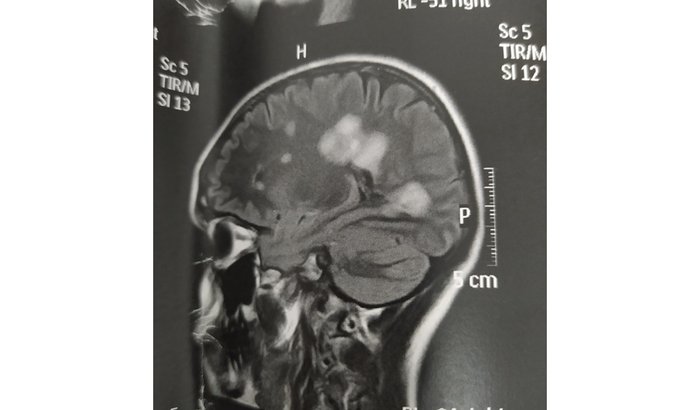

Oi gente, então, é a Isabelly, eu recebi o diagnóstico da esclerose múltipla em março do ano passado, dia 25/03/21. Fui descobrir muitas coisas só em agosto de 21. Essa doença é realmente grave e a minha é agressiva, a EM tumefativa indica uma Em mais grave e agressiva que as demais, e como é uma doença que afeta o sistema nervoso (várias lesões no cérebro) e também coluna (o que indica uma doença mais agressiva ainda) precisa de muitos cuidados e exige muita coisa! Minha visão tá embaçada, o calor pode fazer piorar, nós temos muita intolerância ao calor, preciso tomar vitamina D todo dia, preciso tomar infusões no hospital e preciso ir lá em Fabriciano pra pegar meu remédio, tem as ressonâncias anuais, do liquor, do cérebro, da coluna, as consultas, que no mínimo são 4x ao ano, tenho que ir em Governador Valadares (pois só lá é feita essa coleta) de 6 em 6 meses também pra fazer o JC vírus, eu comecei meu tratamento só esse ano, dia 03/01 e faço o uso do Natalizumabe (medicamento de alta eficácia), tenho JCvirus positivo, o que devido a essa medicação pode fazer com que eu tenha LEMP e a consequência disso é a morte. aí vou poder usar ele durante algum tempo só. Minha doença ainda está ativa. aí tem o ocrevus, o remédio de alta eficácia também mas só o plano de saúde que oferece ele e eu não tenho plano, não tenho dinheiro para arcar com todas essas coisas e ainda continuar meus estudos, não consigo trabalhar agora, não consigo me movimentar bem, enxergar direito. Meu médico disse que achou meu caso sério e que precisamos olhar com muito cuidado, várias coisas podem desencadear outro surto e é realmente muito desgastante tudo que essa doença traz para minha vida. Por favor, quem puder me ajudar eu vou ficar muito agradecida, *a outra vaquinha que fizeram no meu nome foi cancelada, portanto todos os doadores tiveram seu dinheiro de volta.* vou deixar meu pix porque a vaquinha demora duas semanas também pra liberar as doações. Agradeço quem puder me ajudar de alguma forma e qualquer valor é válido. E agradeço muito por quem realmente compreender que é uma situação muito séria e grave. Nós, esclerosados somos ainda muito invisíveis já que é uma doença que acomete entre 35-45 mil brasileiros apenas e eu mesma não sabia antes de tê-la. E sei que muitos desconhecem ela, e todo dia eu aprendo um pouquinho mais, preciso muito de ajuda nesse momento. Obrigada 💛 PIX NEON: 02051207682